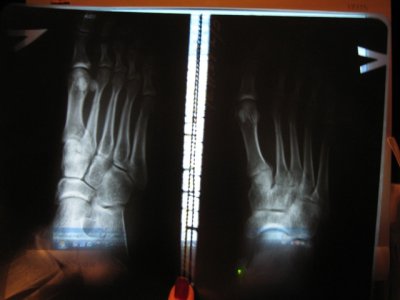

Здравствуйте!Помогите, пожалуйста. Стопу переехала машина. Сломаны 2 плюсневые кости (без смещения). В больнице положили круговую повязку (пластик) на 6 недель. Когда сняли, сделали контрольный снимок, сказали, что срастается. Но на снимке видна трещина. Можно ли считать такое срастание нормальным? Заранее спасибо.

снимки до наложения гипса: